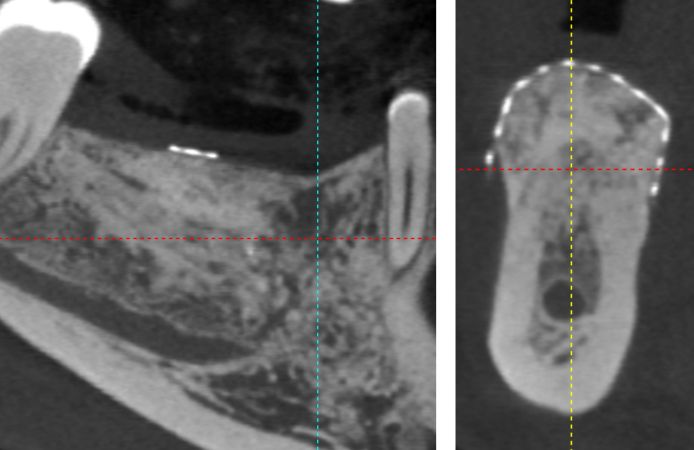

Figure 2.

CBCT evaluation showing a major bone defect in the posterior area of the mandible, with a length of 25 mm and a height of about 10 mm.

CBCT after nine months of healing. Note the level of regenerated bone up to the NeoGen Ti-Reinforced PTFE Membrane.

Figure 10.

CBCT evaluation after nine months of healing, note the vertical and horizontal bone regeneration, filling the whole volume under the NeoGen Ti-Reinforced PTFE Membrane.